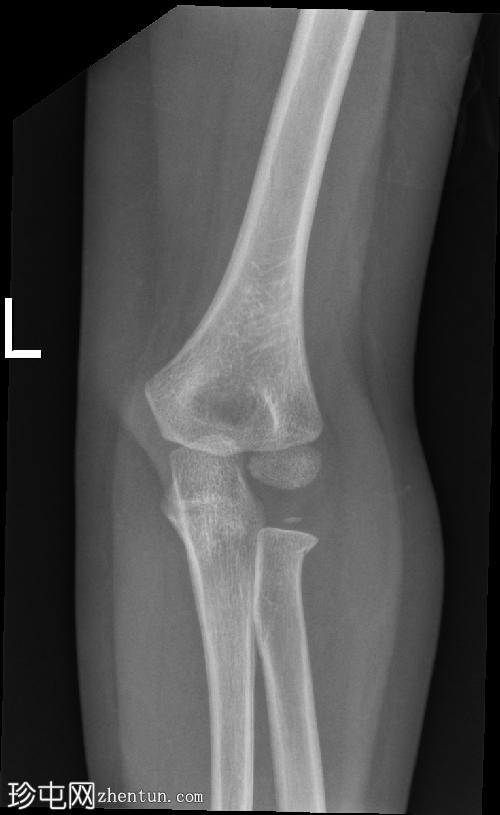

3.png

正面

在正位片和侧位片上,桡骨近端干骺端可见轻微的皮质断裂和不规则,骨折线似乎向骺端延伸。

相关的脂肪垫征(可见前脂肪垫和帆状征,后脂肪垫阳性)进一步支持骨折后关节内积液的存在。

总体而言,骨性对线保持良好,无脱位迹象。

骨化中心与年龄相符。